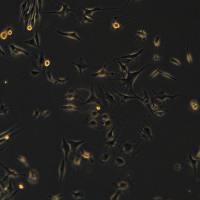

细胞名称:HCT15细胞敲除BRCA2基因细胞系

细胞简称:HCT15 KO-hBRCA2 Cell Line

细胞形态:上皮细胞样

生长特性:贴壁生长